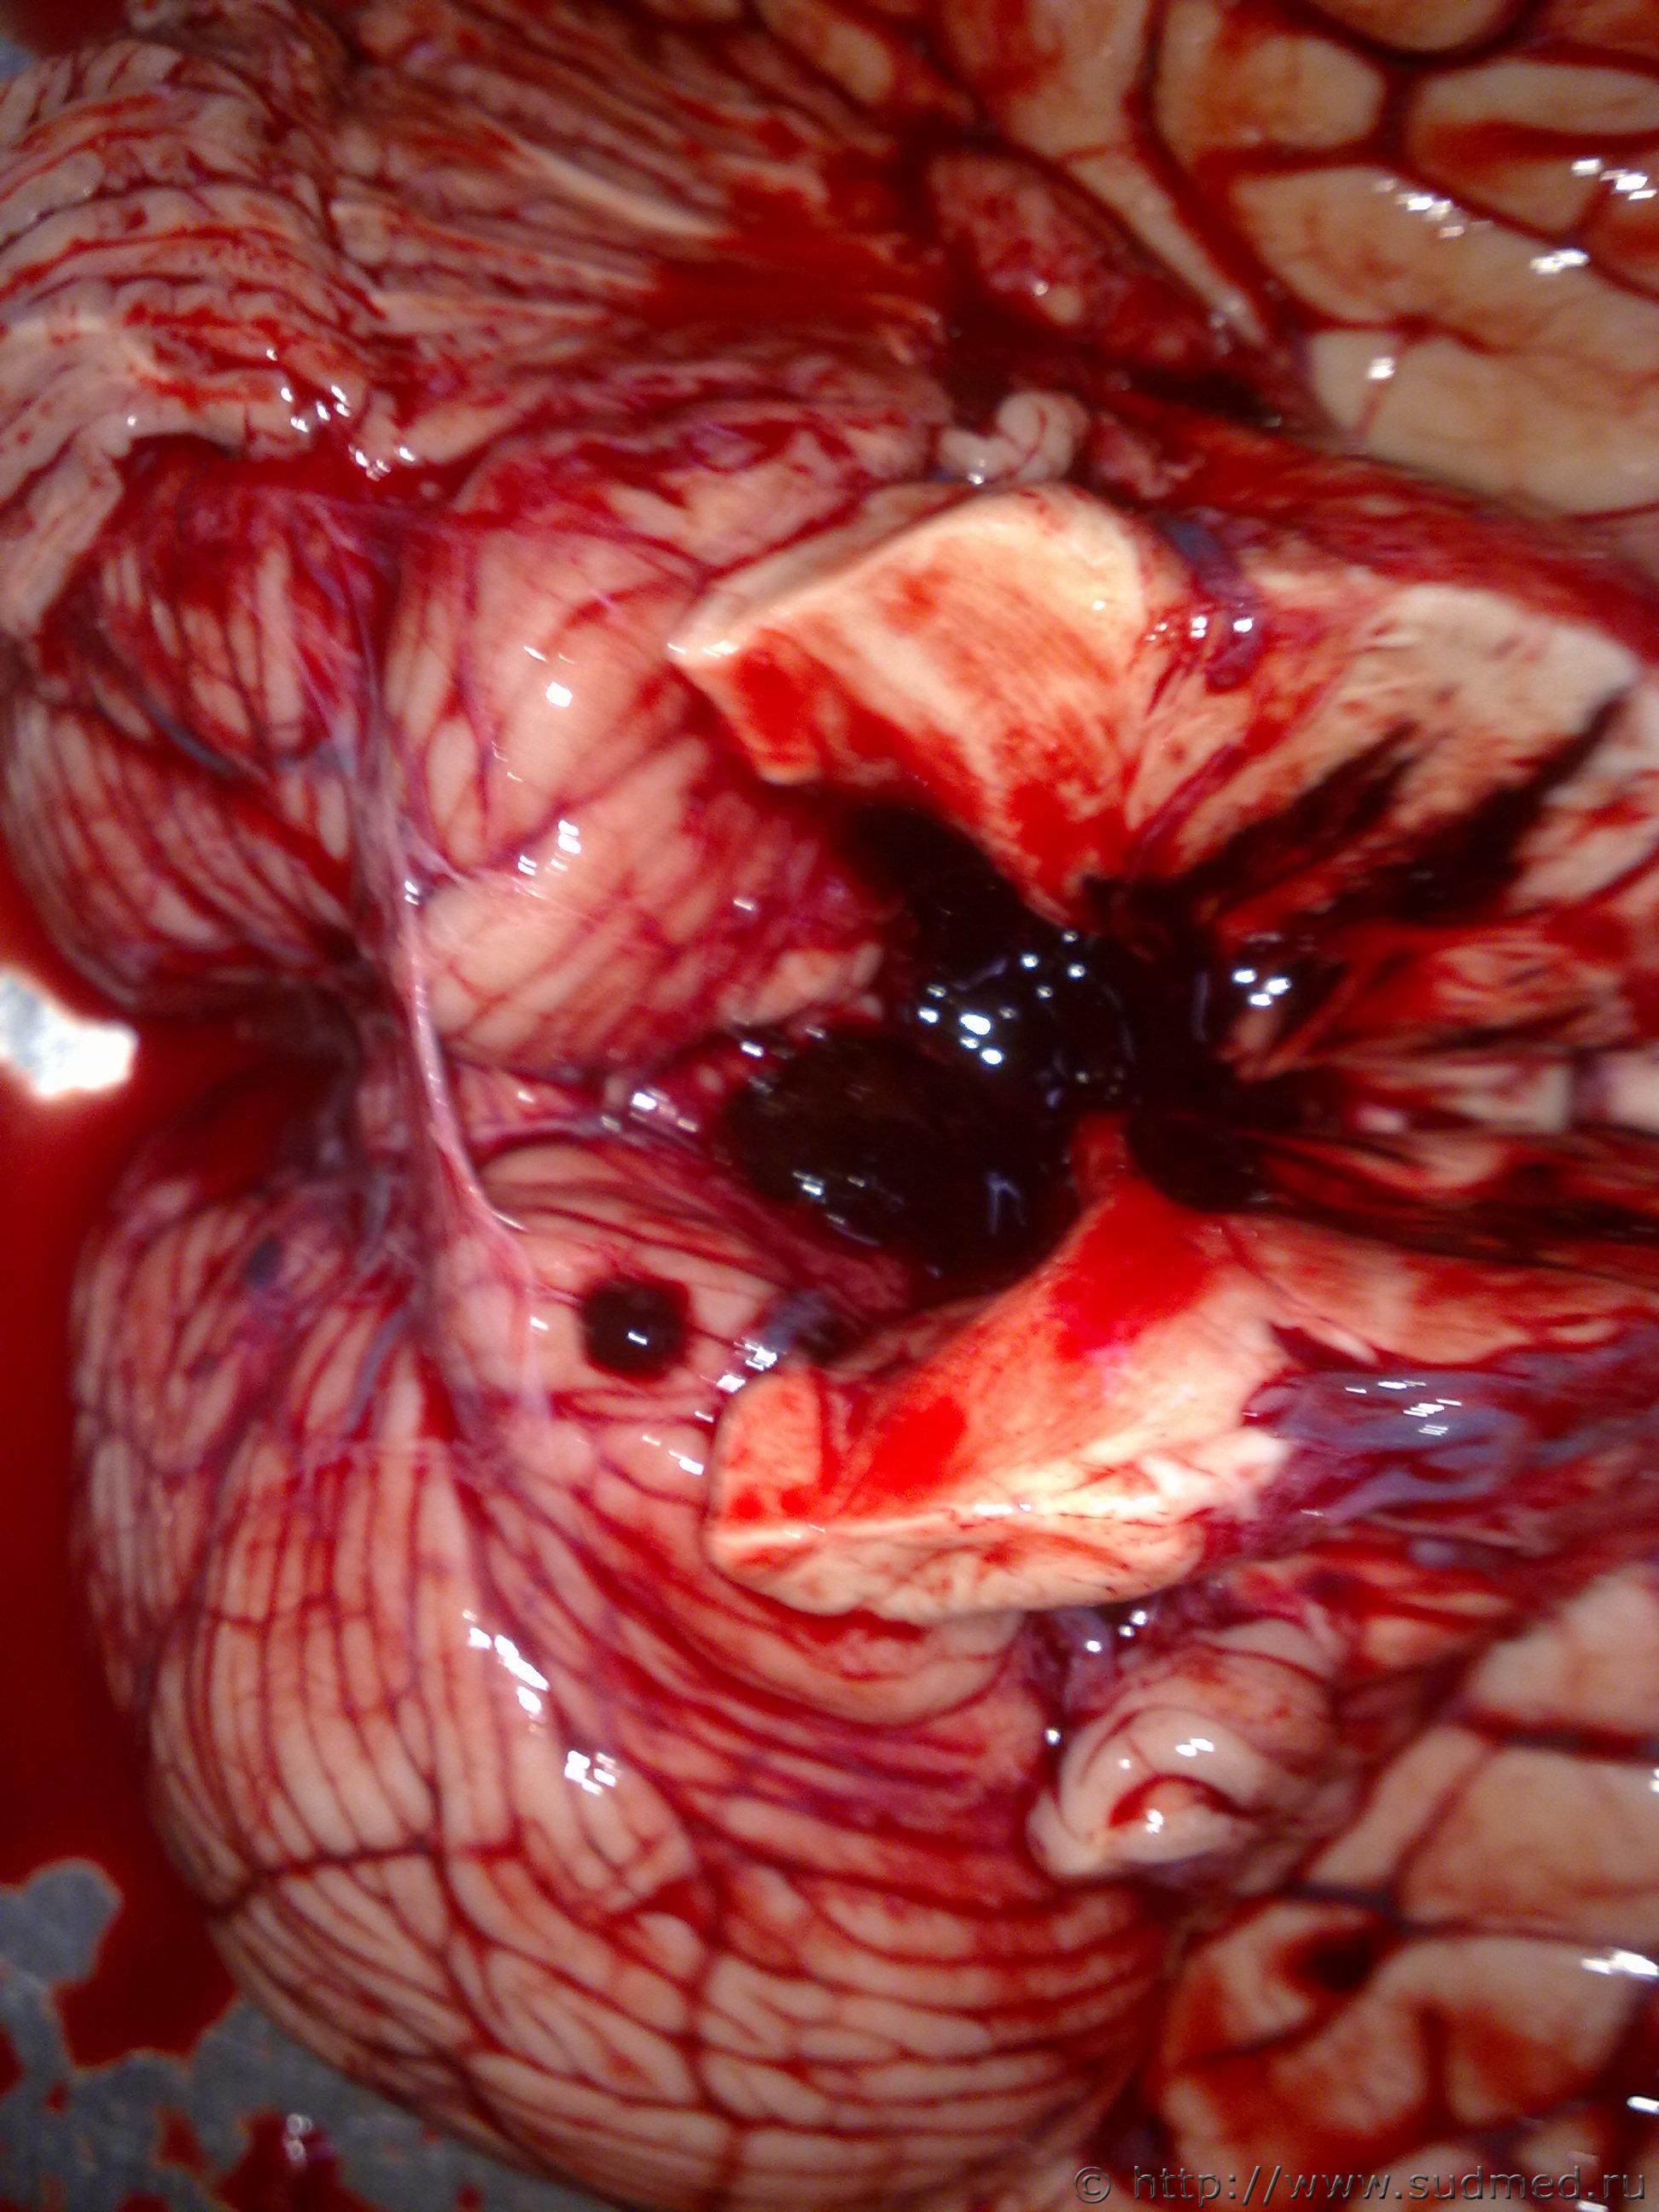

ЗЧМТ, кровоизлияния в ствол мозга